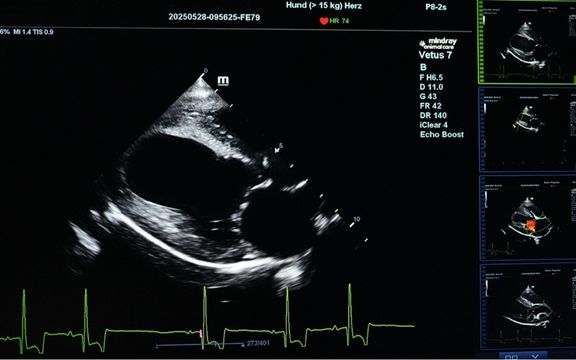

Kardiologie

Mag. med. vet. Tijana Borak betreut unsere Herzpatienten. Sie verfügt über langjähriger Erfahrung auf dem Gebiet der Herz-Sonographie (Ultraschall) ...